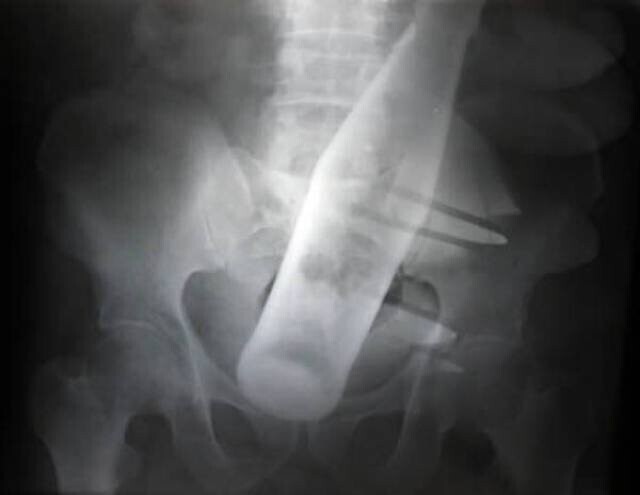

2. Пляшка "Пепсі"